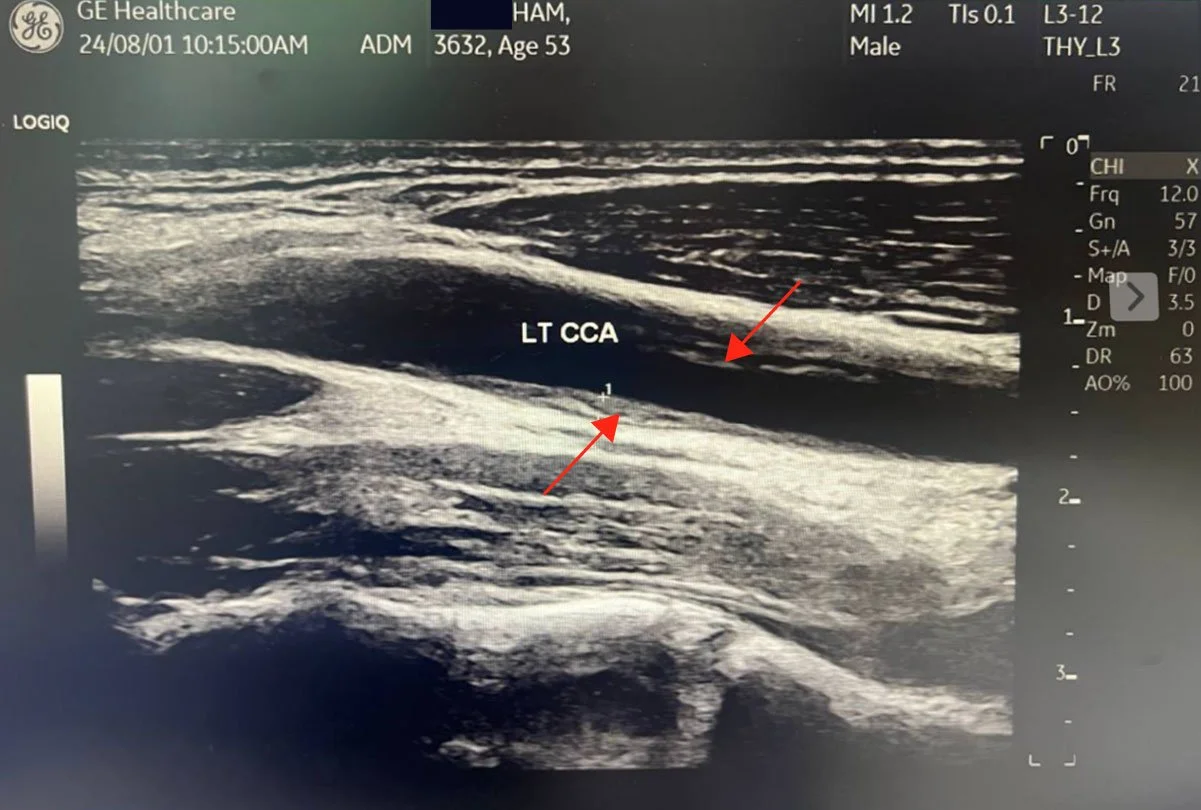

29% Carotid IMT

1.3mm → 0.99mm

0 mm3 Dangerous Plaque

LDNC eliminated